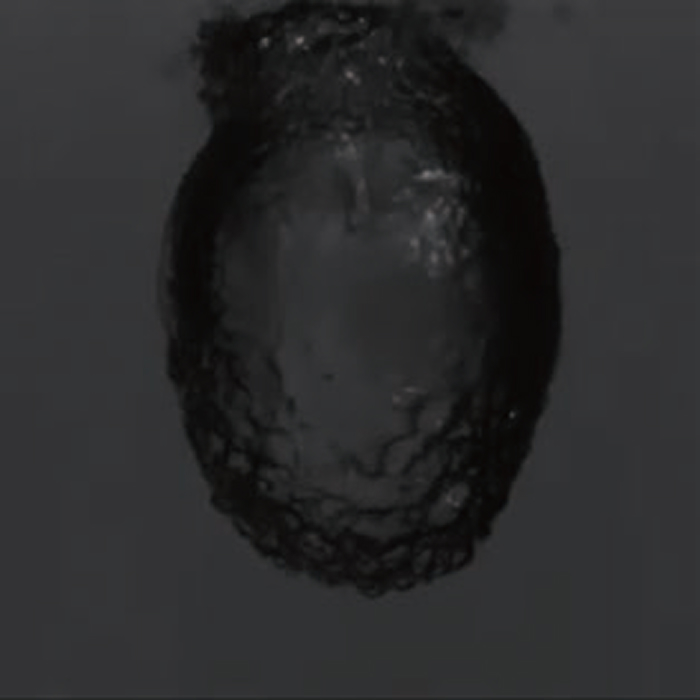

• 図4/TFL 結石破砕片

図4/TFL 結石破砕片